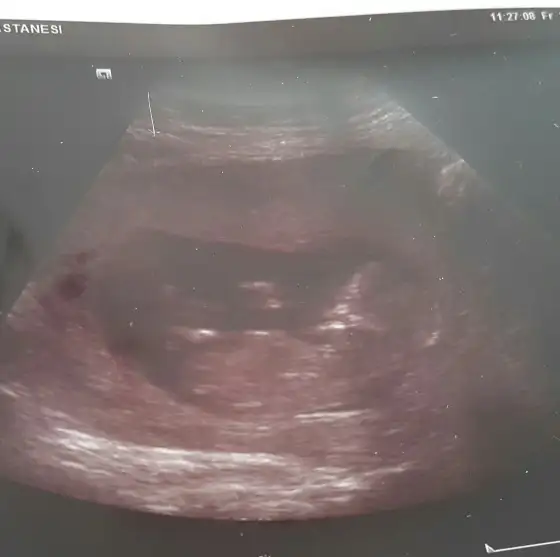

valla bende böyleyim yaaa :) eşim normal badi olmuyo dıe heveslenmıs bırsuru hamıle badisi almış :) soruyolar bende nazar değer die 4 aylık dıyorum

ben geçen hafta havaalanında sıkıntı yaşadım kağıt istediler inanmadılar ilk bankonun arkasından adam fırlayıp kaç aylık hamilesiniz dedi 3 dedim yani tam kaç hafta izin kağıdı var mı yanınızda dedi eşim bankonun arkasında oturan adam fırladı ya bu ne böyle diyor ne yapayım dedim sonra güvenlik hostesler hepsi tek tek sordu 3'e inanmıyorlar diye 4 dedim bende ne diyeceğimi şaşırdım dönüşte bol bir badi giydim çok dikkat çekmesin diye yoksa uçağa binmek için izin kağıdı isticekler diye korktum valla